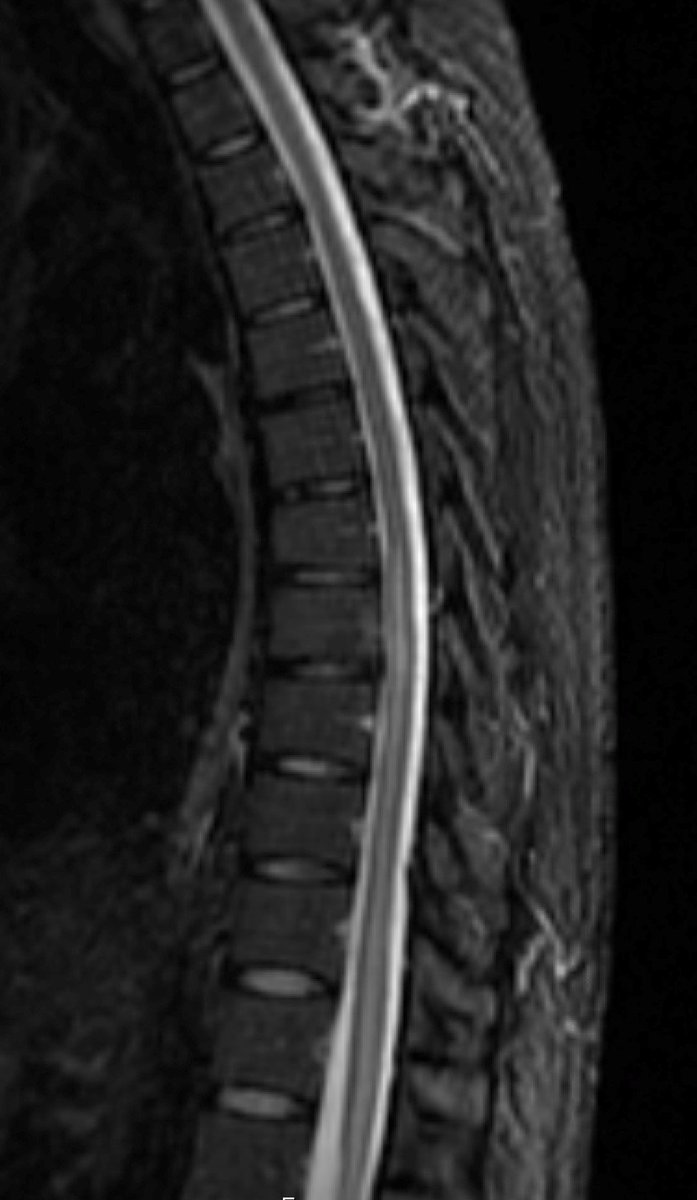

Young gentleman came with severe low back ache following an episode of dengue fever. What do we see here? #spineimaging #medtwitter #radtwitter #FOAMrad #neuroimaging @drvenkimdrd

DrYevSam_Rad's tweet image. Young gentleman came with severe low back ache following an episode of dengue fever. What do we see here?